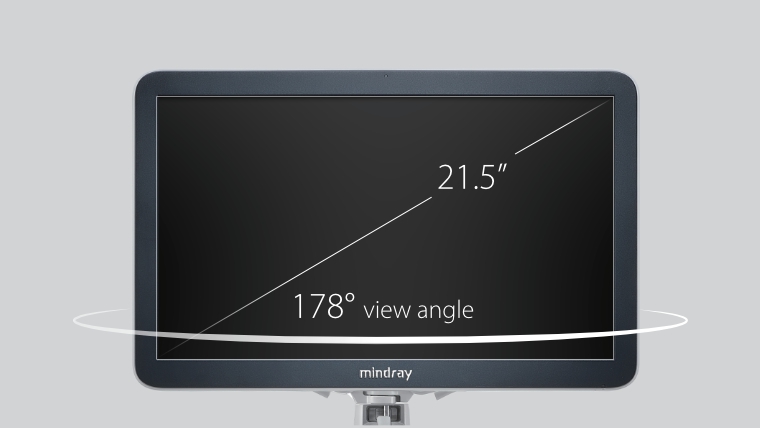

eXceeding Experience

Pengalaman dengan tingkat produktivitas yang tinggi